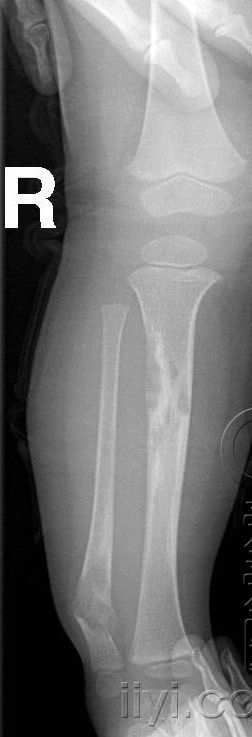

以下是引用zhangzhongshou在2007-5-26 22:17:00的发言:[br]腓骨下端、胫骨中段骨质膨胀改变,胫骨有骨硬化,多考虑胫腓骨骨纤维异常增殖症,伴腓骨病理性骨折。

以下是引用dongjianchun在2007-5-27 12:59:00的发言:[br]胫腓骨噬酸性肉芽肿